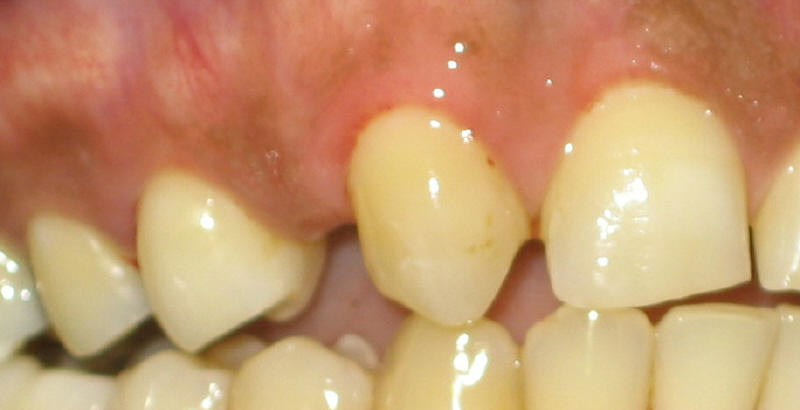

第二个病人也二三十岁,先天性缺失一颗侧切牙。图四显示他一侧上颌前牙,在我们最右手边是中切牙(完整的那一颗),后者的左边是尖牙,那个位置原有应是缺失的侧切牙,所以尖牙因为没有侧切牙而慢慢地往前面移动,几乎移到侧切牙的位置上来了。尖牙后面(左边)是第一和第二前臼齿。理想的治疗是先作牙齿矫正,把尖牙推回它原有的位置(往后面推),然后在侧切牙的位置上植牙,不需要磨任何一颗好牙齿(处女牙,这里可是处男牙)。但是这位老兄是个急性子,不愿意接受慢腾腾的牙齿矫正,他要的是马上的结果。我们只好“遵命”,“下毒手”了:磨小两颗好端端的牙齿做牙桥。为了改善美容,我们必须把尖牙改成侧切牙的样子,也就是说我们需要磨掉许多牙齿组织(图五),术前尖牙比旁边的中切牙长(图四),磨牙后尖牙比中切牙短的多(图五),好像拦腰斩断似,磨短尖牙下面是两个用于比色的牙齿模板;我们还要必须把后面的第一前臼齿磨短。图六显示在牙模型上制作好的牙桥,戴上它后,病人喜出望外(图七)。虽然这个病人牙神经挺争气的,术后没有任何症状(磨牙并发症),但是他作出不少牺牲,失去我们身体最坚硬,最宝贵的东西:牙齿结构,它不能再复原了。植牙仿佛动枪动炮,但是它的靶子却是骨头,后者则会再生,从这点意义上来说,植牙反而更保守。总之,我们做牙桥前必须三思而行。如果牙桥已经做好,我们必须注意口腔卫生,知道如何清洗牙桥。如果您对牙齿美容有兴趣,请看成年专题,第五节牙冠,漂白,美容。

| 图四:侧切牙缺失,尖牙前移 | 图五:尖牙磨掉很多才能做成侧切牙样子 | 图六:牙桥(白色)在牙模型上 | 图七:牙桥刚戴上去,挺逼真的 |